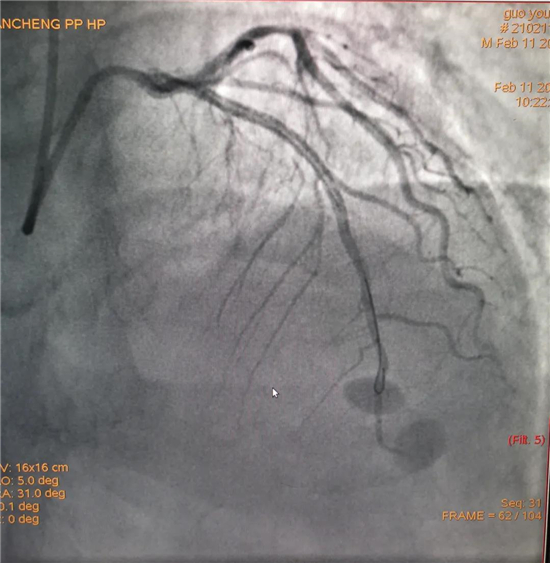

除夕,郭先生無明顯誘因突發胸痛,120急救人員到達現場,心電圖顯示:竇性心律完全性束支傳導阻滯。信息立刻發送到胸痛中心介入微信群中,心內科值班醫生初步診斷為急性廣泛前壁心肌梗死,必須盡快進行急診支架治療,開通血管。值班醫生電話指導院前治療,并立即啟動胸痛綠色通道,24小時備班的介入治療團隊立即到位,9:30患者被送到導管室行冠脈介入診療,9:40急診PCI手術隨之開始,冠脈造影檢查提示左前降支閉塞,植入支架,堵塞的血管被順利打通,患者癥狀緩解,手術非常成功,10:20患者被送往病房進一步治療。